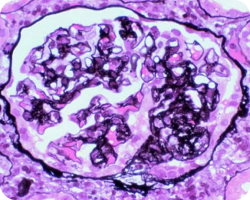

Эндокапиллярная пролиферация

Image

Связана с более быстрой потерей функции почек и худшей почечной выживаемостью. При этом использование иммуносупрессии может маскировать прогностическую ценность Е в отношении почечных исходов. Данный признак указывает на необходимость исследования применения иммуносупрессивной терапии22.